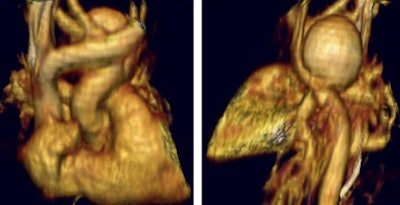

"Another child presented with pericarditis," Greenberg said. "But when the CT was done, we found this large ductal aneurysm which was filled with MRSA (methicillin-resistant staph aureus) -- certainly a child that you'd like to get in and out quickly."

| In an infant presenting with pericarditis, MDCT showed a large mycotic aortic aneurysm. |